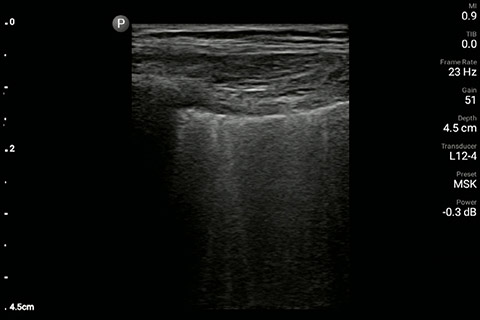

The patient had reduced LV systolic function without new or severe valvular pathology, a dilated, non-collapsing IVC, and diffuse B lines (left greater than right) on lung ultrasound imaging.

M-mode demonstrating lung sliding

Inferior vena cave